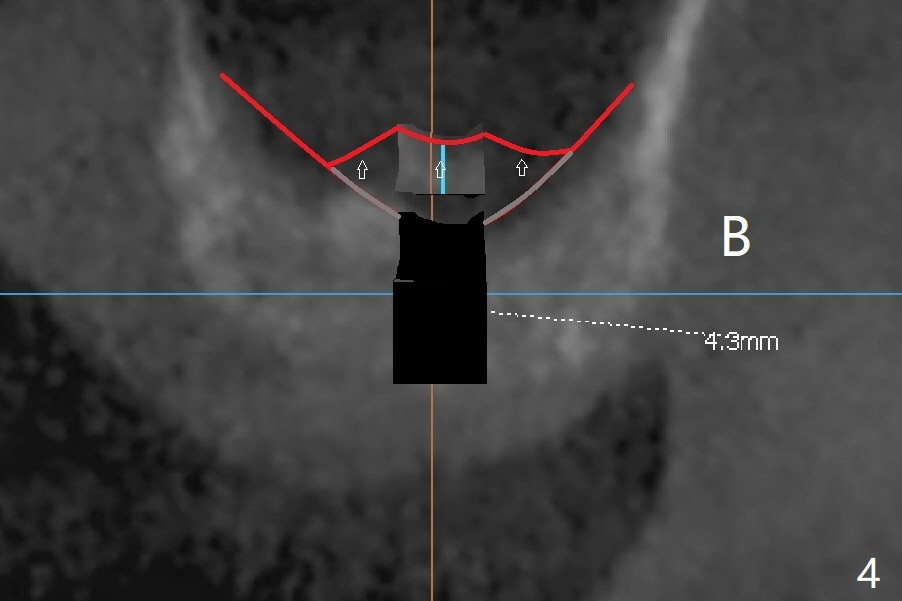

A 48-year-old man returns for CT 4.5 months post infected implant removal with bone graft at #15. The bone height reduces from 6-10 mm to ~ 4 mm (Fig.1). To place a 5x7.3 mm implant (Fig.2), initial osteotomy for ~3 mm in depth and in diameter will be aided by guided surgery (Fig.3 (red line: sinus membrane)). Internal sinus lift is going to be conducted with Magic Lifter free hand or in the middle of the tube (Fig.4 arrows). The specially designed lifter is able to lift the sinus floor without tearing the membrane. To prevent and repair membrane injury, one or 2 pieces of PRF membrane will be inserted underneath the lifted structures (Fig.5 yellow), followed by bone graft (green circles). Then 3.5-4.5 mm taps will be used with guide to further expand and condense the osteotomy. With more graft to be placed, the 5x7.3 mm implant will be placed (Fig.6 pink).